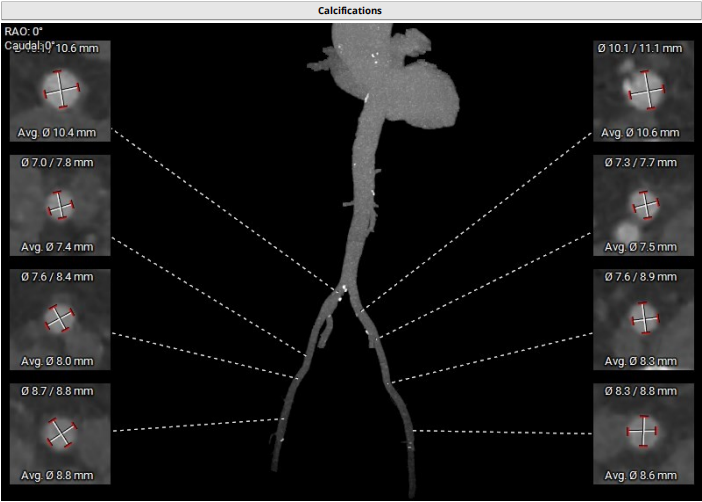

血管入路评估:腹主动脉及髂总动脉可见散在钙化,右侧髂外动脉最细5.8 mm(平均径5.9 mm),左侧髂外动脉最细5.8 mm(平均径6.1 mm)。双侧股动脉分叉点较高。23#瓣膜选用22F大鞘。

血管入路评估:主动脉弓部角度小,右侧股动脉最细 7mm,左侧股动脉最细7.3mm。双侧股动脉穿刺点无明显钙化。